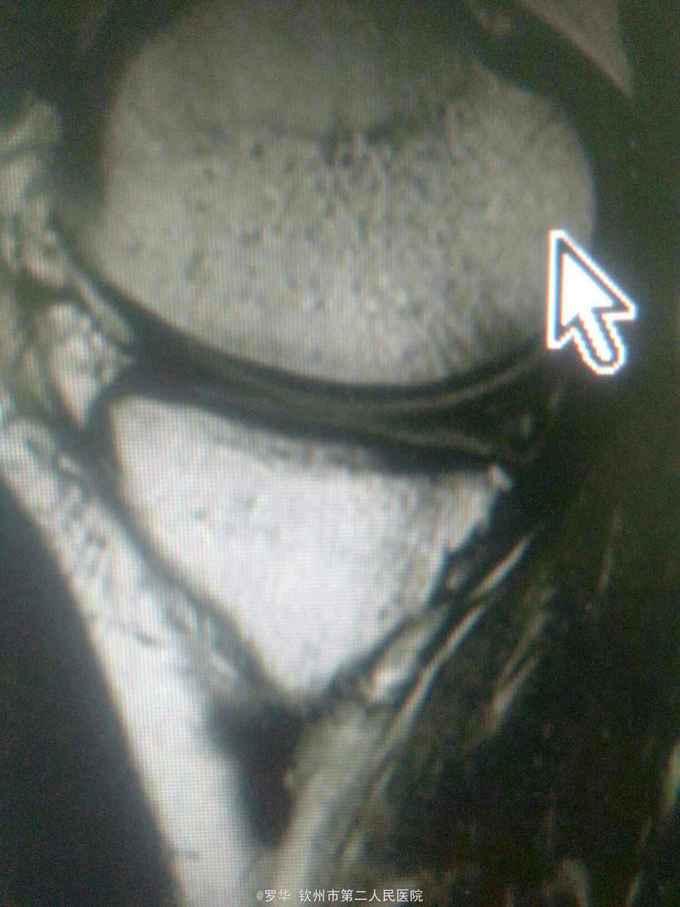

主诉:扭伤致左膝关节活动受限3月余。病史:患者男性,31岁,于入院3月余前扭伤左膝关节,致左膝关节肿痛、活动受限,尚可站立行走,但不能剧烈运动及重体力劳动,曾行磁共振检查提示左膝前交叉韧带损伤,半月板损伤,现为进上一步治疗入院。

查体:左膝关节无明显压痛,前抽屉试验阳性,侧方应力试验、麦氏征、研磨试验均阴性,膝关节屈伸活动可,余查体未见特殊。 辅查:膝关节磁共振提示左前交叉韧带损伤,左膝关节半月板损伤。

诊断:左膝关节前交叉韧带断裂,左膝关节半月板损伤。 治疗:予硬外麻下行左膝关节前交叉韧带重建术。